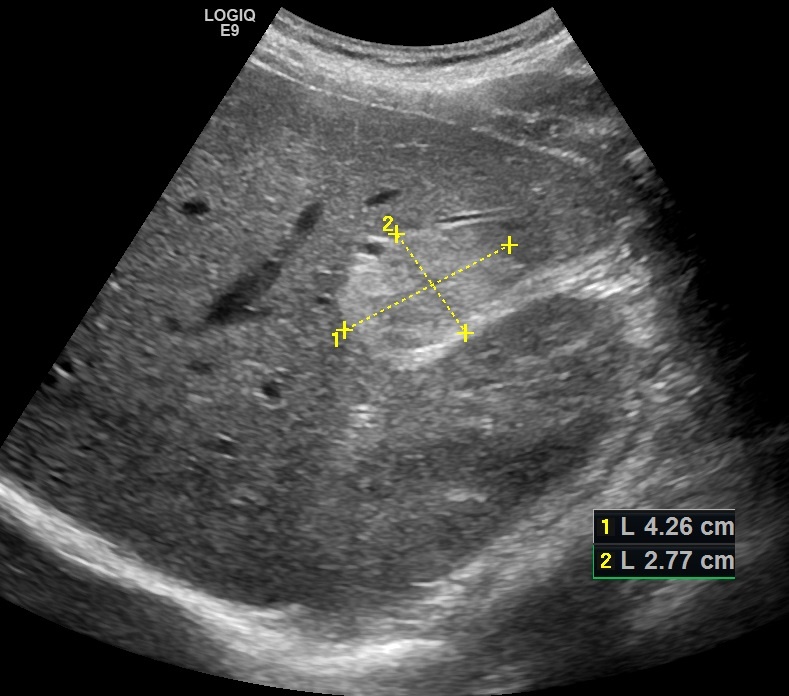

При ультразвуковом исследовании по висцеральной поверхности правой доли, вплотную к контуру правой почки определяется крупное гиперэхогенное образование с четкими неровными бугристыми контурами.

Рис. 01. Кавернозная гемангиома печени.

Структура образования выражено неоднородная, с множественными участками пониженной эхогенности.

Подобная неоднородность структуры гемангиомы свидетельствует о наличии более крупных полостей в ее структуре, т. е. эту гемангиому следует расценивать как кавернозную. В остальных отделах печени определяются несколько более мелких гиперэхогенных образований однородной структуры — капиллярные гемангиомы.